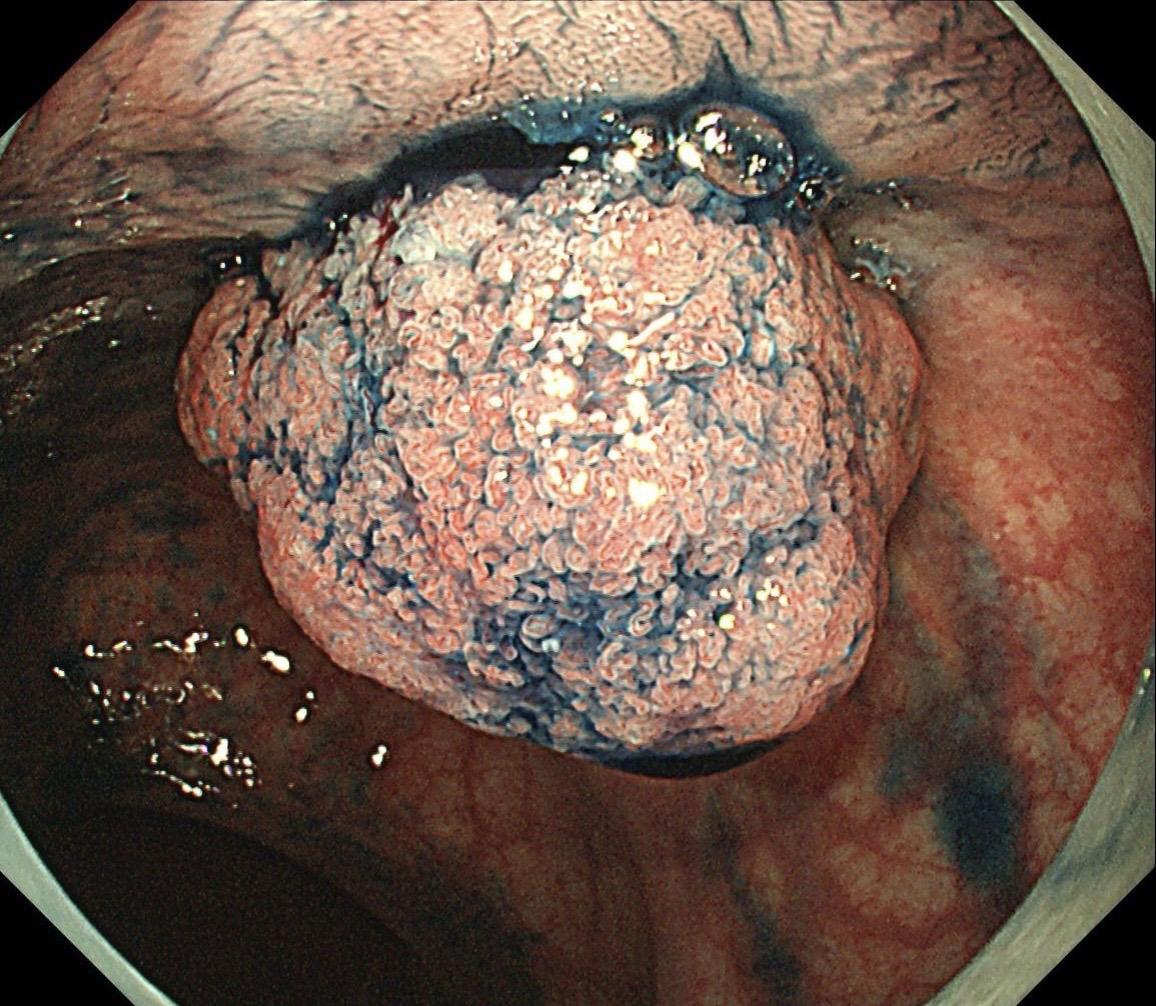

低位早期直肠Ca.男,37岁,大便带血1月,距齿状线2cm,ESD切除,还好来得及时~